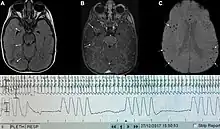

| Graph showing Biot's respiration and other pathological breathing patterns. | |

Biot's breathing or ataxic breathing, is an abnormal pattern of breathing characterized by variable tidal volume, random apneas, and no regularity.[1] It is named for Camille Biot, who characterized it in 1876.[2][3]

Biot's respiration is caused by damage to the medulla oblongata and pons due to trauma, stroke, opioid use, and increased intracranial pressure due to uncal or tentorial herniation.[1][4] Often this condition is also associated with meningitis.[2]